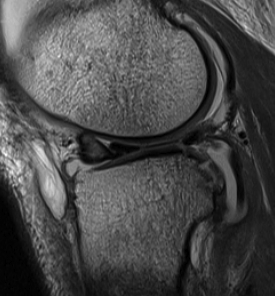

1. Longitudinal Tears

Most common

- vertically oriented tear parallel to edge of meniscus

- usually of posterior part of meniscus

- may occur in either meniscus

- extent varies

B. Complete

C. Bucket handle

- displaces into intercondylar notch

- may be central or peripheral

- cause of locked knee

- can damage chondral surface over time